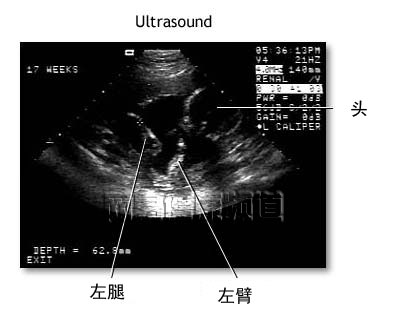

利用超声探头在病人的腹部进行轻柔地滑过,显示器上就可看到腹内的一些情况。

超声传感器发出人耳听不见的超声波,当超声通过腹部密度不同的组织时,会折返回强弱不等的声波。电脑将把这些强弱不同的声波转化成相应的图像并显示在屏幕上。

由于显示在屏幕上仅是不大清晰的黑白图像,因此不必对超声的诊断结果寄于太大的期望。但这种非伤害的性的检查对了解胎儿的手脚及头部的发育情况是很有帮助的。